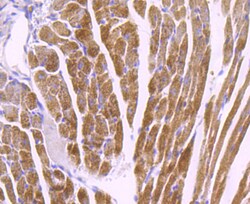

COX4 Polyclonal Antibody for Western Blot, ICC/IF, IHC (P), Flow

| Flow Cytometry, Immunohistochemistry (Paraffin), Western Blot, Immunocytochemistry | |

| Human, Mouse, Rat | |